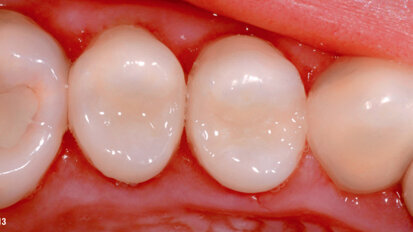

Nano-hybrid ORMOCER for the bulk-fill technique in the posterior region

Direct composites in posterior teeth are a part of the standard therapy spectrum in modern dentistry. The excellent performance of this form of restoration ...